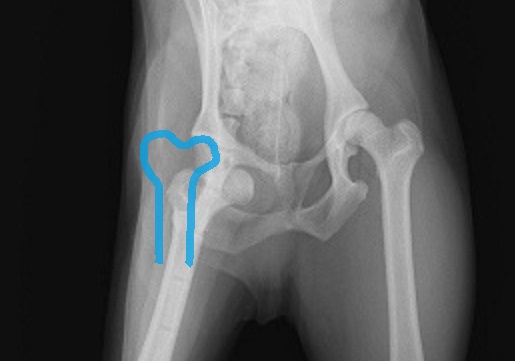

股関節の脱臼 ~その2~

股関節の脱臼を起こすと、

足を上げたまま、

地面に着けなくなります。

おさらいです。

上の写真を見てください。

青の位置にあるはずの股関節が、

脱臼して、

緑の位置になってしまっています。